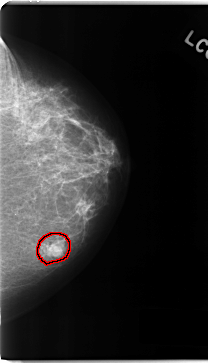

C_0161_1.LEFT_CC

LEFT_CC LINES 4712 PIXELS_PER_LINE 2696 BITS_PER_PIXEL 12 RESOLUTION 50 OVERLAY

FILE: C_0161_1.LEFT_CC.OVERLAY

TOTAL_ABNORMALITIES 1

ABNORMALITY 1

LESION_TYPE MASS SHAPE LOBULATED MARGINS MICROLOBULATED

ASSESSMENT 5

SUBTLETY 5

PATHOLOGY MALIGNANT

TOTAL_OUTLINES 1

BOUNDARY